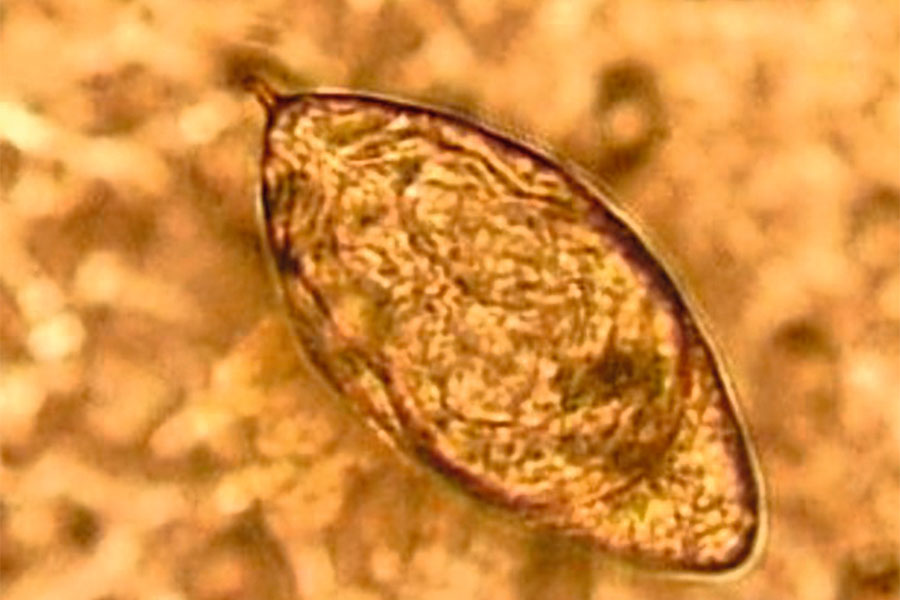

So sehen die Eier des Saugwurmes Schistosoma haematobium, Erreger der gefährlichen Infektionskrankheit Bilharziose (Schistosomiasis), unter dem Mikroskop aus.

Vera Kühne